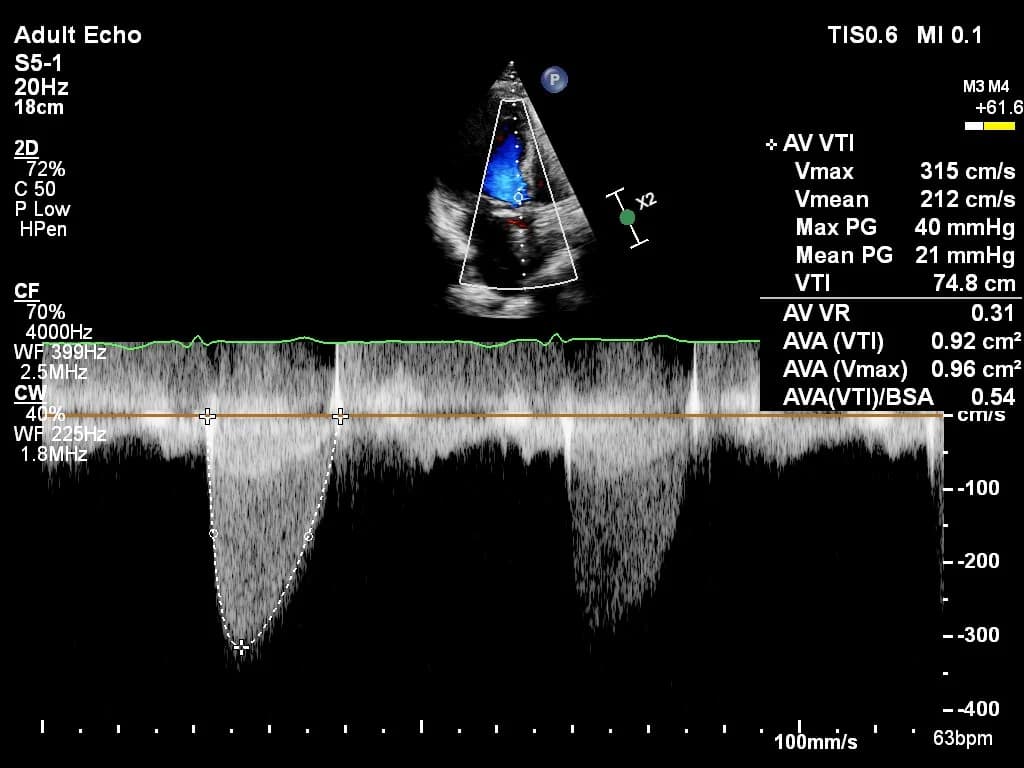

Practice with anonymized echocardiography cases from real clinical encounters.